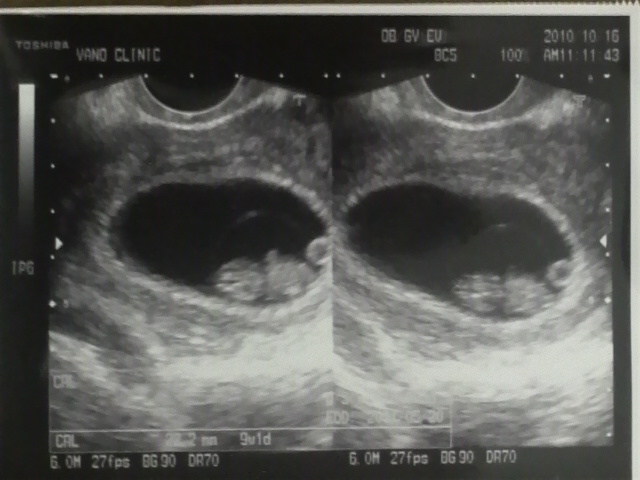

今日は妊婦検診に行ってきました!!!(・∀・)

えーっと、いま9週目ってとこらへんらしいよ。

超音波検査では、前よりももっとおっきくなってて

頭とか足とかがおぼろげに判りだしました(*´∀`*)

あと、心臓がトクトク動き始めてた!!!

見えるんだよ!!!超神秘!!!(*´∀`*)